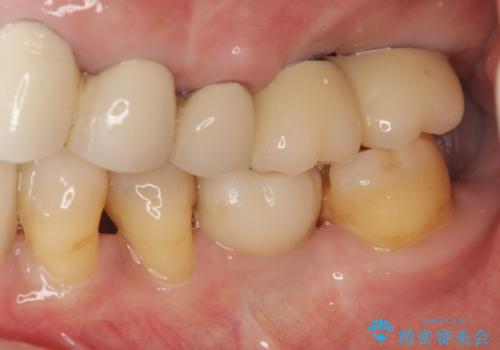

- 他院で治療した左上のセラミック部位の痛みを訴えて来院されました。

支台となる小臼歯に過大な負担のかかる遊離端ブリッジが装着されていたため、義歯かインプラントを用いた再補綴計画を提案しよりしっかりと噛めるインプラント治療をご希望されました。

力学的に無理のある遊離端ブリッジをインプラントを用いて長期的な予後を見込める補綴状態へと改善しました。